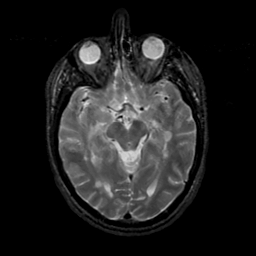

MR Study #17, July 7, 1991 -- Slice #21